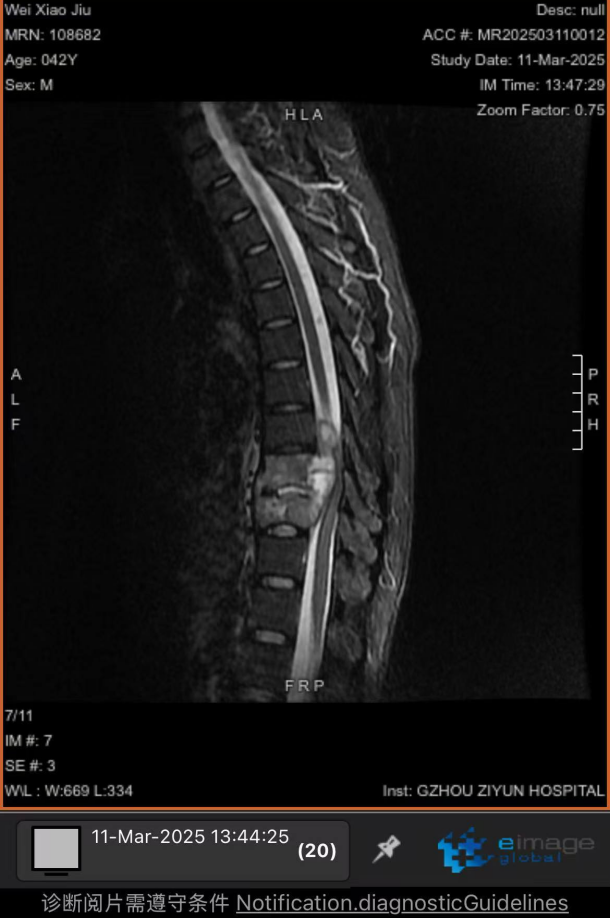

以為是干活勞累,卻突發(fā)癱瘓 “我以為是最近做活路太累了,導(dǎo)致的腰酸背痛,哪曉得突然就癱了!真的感謝周醫(yī)生他們的幫助,把我救回來(lái)了!”談起這番經(jīng)歷,張先生仍心有余悸。 據(jù)悉,今年三月初,42歲的張先生(化名)因胸背疼痛一個(gè)月未進(jìn)行相關(guān)治療,伴隨疼痛進(jìn)行性加重后,入院前3天出現(xiàn)雙下肢無(wú)力、不能行走、大小便失禁等情況。入院時(shí),體查其雙下肢肌力為0,自肋弓以下喪失知覺(jué),無(wú)法坐立,且影像學(xué)檢查顯示,其胸椎上段被結(jié)核性膿腫及壞死骨嚴(yán)重壓迫,脊髓持續(xù)受損。 "每耽誤一分鐘,神經(jīng)壞死風(fēng)險(xiǎn)就增加一分?;颊吣茉僬酒饋?lái)的可能也就減少一分,對(duì)患者家庭是災(zāi)難性后果,我們必須為他爭(zhēng)取時(shí)間。"貴陽(yáng)市公共衛(wèi)生救治中心外三科副主任周波告訴記者;通常情況下,脊柱結(jié)核手術(shù)需2-3周抗結(jié)核治療后再行手術(shù)。但面對(duì)張先生不斷惡化的脊髓損傷,他們必須與患者一同與時(shí)間賽跑:打破常規(guī)的急診手術(shù)決策,進(jìn)過(guò)迅速且嚴(yán)謹(jǐn)?shù)臅?huì)診決策后,靜脈給予一次抗癆治療,團(tuán)隊(duì)當(dāng)機(jī)立斷采用"脊柱前后路聯(lián)合"急診手術(shù)為張先生進(jìn)行施救。“我們首先從前路開胸,清除椎體前方膿腫及壞死組織,植入鈦網(wǎng)替代部分椎體功能,由于椎體跳躍性骨質(zhì)破壞,前路固定不牢固,立即行后路手術(shù),通過(guò)椎弓根釘棒系統(tǒng)實(shí)現(xiàn)脊柱三維穩(wěn)定,再次行后路減壓,雙路徑手術(shù)一次性徹底清除病灶,減壓更充分,復(fù)發(fā)幾率更小。 患者術(shù)前X片 患者胸部CT 患者胸椎核磁共振 術(shù)后復(fù)查的X線 該患者在術(shù)后第一天身體感知覺(jué)有較明顯恢復(fù),第5天開始腳趾恢復(fù)活動(dòng),兩周時(shí)肌力恢復(fù)至3級(jí)以上,截至昨日記者在現(xiàn)場(chǎng)目睹,雙腿已經(jīng)可以自主抬放。周波副主任表示,急性脊髓損傷的黃金救治窗口極短,聯(lián)合入路既能快速減壓又確保長(zhǎng)期穩(wěn)定性,這是恢復(fù)超預(yù)期的關(guān)鍵。預(yù)計(jì)一個(gè)月左右,這位患者就能重新自主行走了。 本次手術(shù)團(tuán)隊(duì)的幾位醫(yī)生正在叮囑患者出院后的注意事項(xiàng) 左起:羅善鵬,石頭,周波,左樂(lè) 專家提示: 腰痛≠腰椎勞損 這些信號(hào)要警惕 針對(duì)近年多發(fā)的"腰痛誤診"現(xiàn)象,周主任特別提醒:腰椎結(jié)核多以持續(xù)性腰痛為主,多伴低熱、盜汗、體重下降等結(jié)核中毒癥狀;而腰椎間盤突出典型表現(xiàn)為腿痛腿麻等。一定要注意的是當(dāng)出現(xiàn)腰痛合并下肢無(wú)力、大小便功能障礙時(shí),無(wú)論屬于哪一種情況都需立即就醫(yī)。 據(jù)統(tǒng)計(jì),我國(guó)結(jié)核感染人群超2億,其中5%-10%的肺外結(jié)核可累及脊柱。專家強(qiáng)調(diào),骨結(jié)核雖發(fā)病率低,但致殘率高,早期規(guī)范治療可避免災(zāi)難性后果。 專家簡(jiǎn)介 周波,男,43歲,副主任醫(yī)師,中國(guó)抗癆協(xié)會(huì)結(jié)核病健康促進(jìn)分會(huì)委員,中華醫(yī)學(xué)會(huì)貴陽(yáng)市骨科分會(huì)委員、貴陽(yáng)市康復(fù)醫(yī)學(xué)會(huì)委員,貴陽(yáng)市骨科質(zhì)量委員會(huì)委員,貴陽(yáng)市艾滋病性病防治協(xié)會(huì)委員,中國(guó)中醫(yī)藥信息學(xué)會(huì)骨科分會(huì)委員,從事臨床醫(yī)學(xué)骨外科專業(yè)15余年,擅長(zhǎng)脊柱結(jié)核及其截癱患者的治療,搶救脊髓功能,擅長(zhǎng)骨與關(guān)節(jié)結(jié)核的診治,髖、膝關(guān)節(jié)置換的治療,術(shù)后療效顯著,有效減少患者的致殘率。在國(guó)內(nèi)學(xué)術(shù)核心雜志發(fā)表學(xué)術(shù)專業(yè)文章15篇。